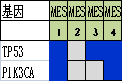

通过进一步基因表达谱测序���,对组织形态学和免疫组化水平界定的TNBC亚型的基因变异情况进行分析����,筛选各亚组之间的差异表达基因及表达意义探究��,结果显示���:1.免疫治疗相关的生物标记物MSI-H��、TMB-H����,作为一个低频发生事件����,在TNBC中不太可能常规作为免疫治疗有效性的评估手段��;TNBC的MSI发生机制可能与结直肠癌不同����、突变热点不同��。2. 整个研究队列中基因表达存在明显差异��,充分显示了患者个体间差异的存在����,从分子水平揭示了TNBC是一种高度异质性肿瘤��。3. TP53基因变异率发生最高��,提示在TNBC形成中可能扮演非常重要的角色����。4. TNBC分型的基因表达聚类分析方面存在差异(图2)����,这些差异基因参与了多种不同的生物学通路��,筛选特异的分子标记物或靶向治疗的靶点以期指导临床治疗���。

图2. 基于组织形态学及免疫组织化学标记物的TNBC亚型的基因表达聚类分析